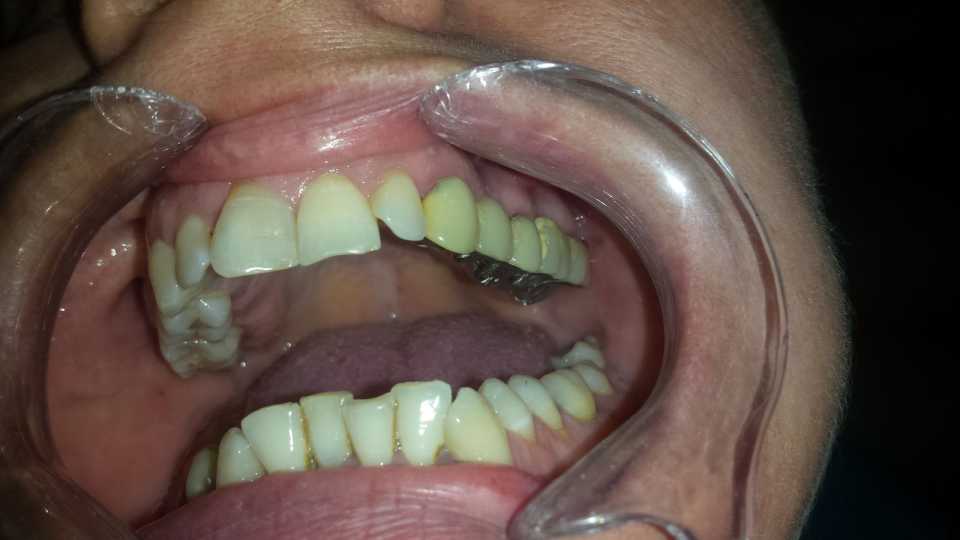

Pacienta s-a prezentat în cabinet din motive estetice și funcționale, acuzând sângerări gingivale și un miros neplacut. Am îndepărtat vechea lucrare, am refăcut tratamentele de canal, bonturile protetice și am slefuit bonturile cu prag.